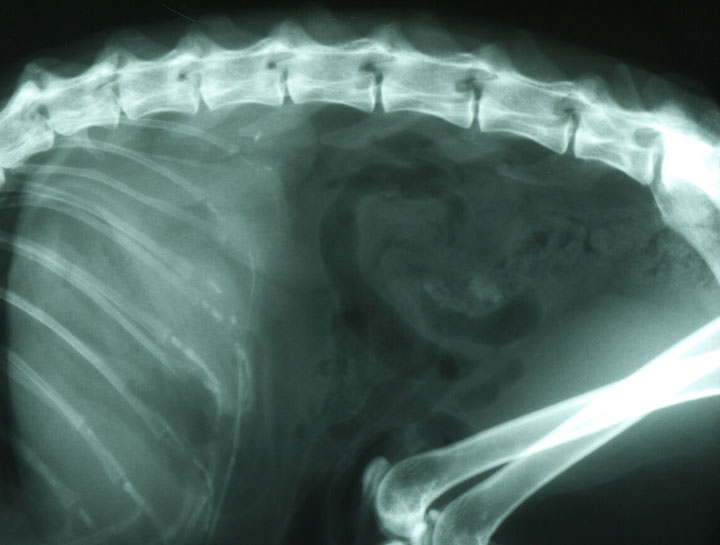

Pet Digital Radiology

Digital x-rays assist in diagnosing illness & injury.